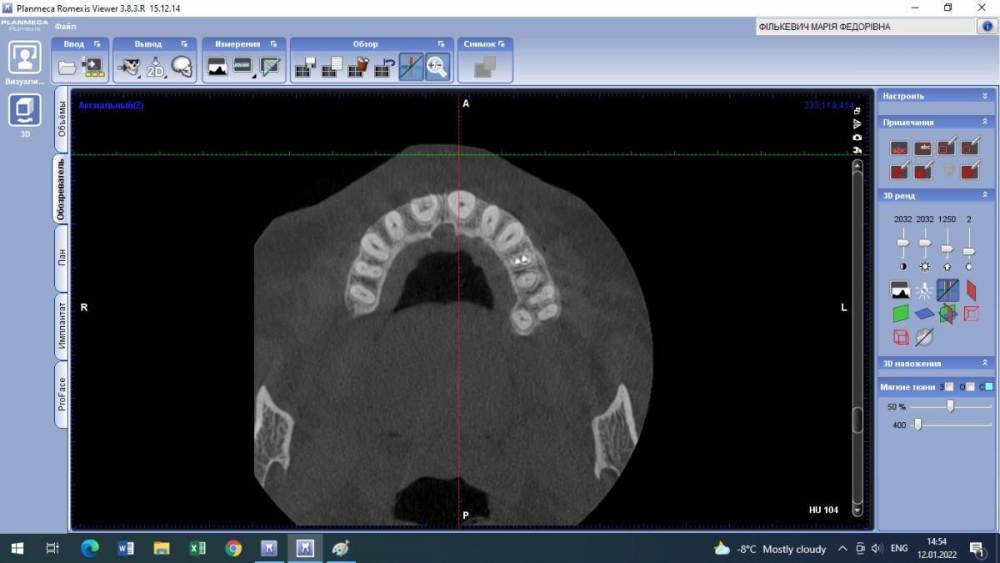

Lyubanya Опубликовано 12 января, 2022 Поделиться Опубликовано 12 января, 2022 Здравствуйте, коллеги. Вот такой случай. 11 зуб, пациентка 1963 г.р. Найдено случайно на КТ, делала его 3.09.21 по другому поводу, я взяла посмотреть для эндо премоляров. Визуально во рту вижу легкую розоватость пришеечно, и есть место, где цепляет зонд. Вопросов много. Каков точный диагноз? И что делать с этим зубом? Есть ли у него шансы пожить еще? Я так понимаю по возможности делается эндо в таком зубе. Если есть шансы то какова тактика? Ссылка на комментарий

Александр23712 Опубликовано 15 января, 2022 Поделиться Опубликовано 15 января, 2022 @Lyubanya Лично я бы, если не беспокоит, пока не трогал, но пациентку бы предупредил и кт показал. Может она ничего и не поймет, зато, когда/если заболит, придет к вам. Процесс прямо чуть ниже шейки. Как я понимаю, чтобы такое лечить, вам надо сначала лоскут откинуть, дальше в зависимости от кортикальной пластинки. Но у композита к дентину спорная адгезия ? . По поводу эндо не представляю, зачем депульпировать зуб раньше срока. Сделайте прицельный еще в 2 проекциях, интересно посмотреть Ссылка на комментарий

Lyubanya Опубликовано 15 января, 2022 Автор Поделиться Опубликовано 15 января, 2022 9 часов назад, Александр23712 сказал: @Lyubanya Лично я бы, если не беспокоит, пока не трогал, но пациентку бы предупредил и кт показал. Может она ничего и не поймет, зато, когда/если заболит, придет к вам. Процесс прямо чуть ниже шейки. Как я понимаю, чтобы такое лечить, вам надо сначала лоскут откинуть, дальше в зависимости от кортикальной пластинки. Но у композита к дентину спорная адгезия ? . По поводу эндо не представляю, зачем депульпировать зуб раньше срока. Сделайте прицельный еще в 2 проекциях, интересно посмотреть Какая конкретно это резорбция? Разряжение вокруг основного канала = внутренняя резорбция корня? Или нет? Просто пыталась найти инфо, и нашла что внутренние это эндо. Но если можно наблюдать, то я только за) Пациентка работает у нас санитарочкой и я совсем не хочу ей лишнего стресса и тем более потери зуба. Хотела с главврачом обсудить, но пожалуй пока не буду. У меня на КТ нашлось новообразование, он ходил давил что надо удалить зуб вместе с ним. В итоге спустя полгода оказалось, что это цементно-костная дисплазия и ничего удалять не нужно. Спасибо Рогацкину.? И как мне сделать две проекции на пленочном?? 9 часов назад, Дмитрий Л. сказал: Реставрация без эндо; риск рецессии. Имеете ввиду перекрыть то место, где зонд цепляется? Ссылка на комментарий

Дмитрий Л. Опубликовано 15 января, 2022 Поделиться Опубликовано 15 января, 2022 Это инвазивная цервикальная резорбция, связи с пульпой нету, хирургически можно откинуть лоскут и реставрировать. Риск рецессии. Другое лечение - выжидание, риски прогресса с потерей зуба, смотрите на возраст пациента. 1 Ссылка на комментарий